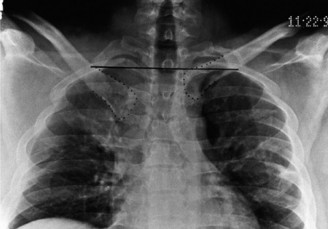

Standard radiography includes an anteroposterior view of the chest and a Serendipity view. The Serendipity view is obtained with the patient supine and the x-ray beam angled 40 degrees cephalad, centered on the manubrium. This view allows for comparison of the bilateral medial clavicles. In an anterior dislocation, the affected clavicle will appear superior to the uninjured side. In a posterior dislocation, the affected clavicle will appear inferior.